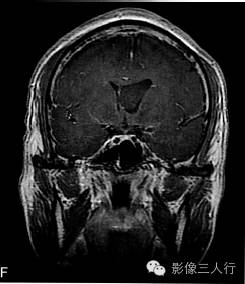

A.T2WI横断面;B.T1WI横断面;CFLAIR冠状面;D、E、F.增强横断面、矢状面、冠状面;G、H.CT平扫、增强;I.HE×100

肿瘤呈类圆形,边界清楚,位于左侧脑室前角及室间孔区,左侧脑室前角、三角部及左侧脑室后角扩张积水。MRI平扫T2WI(图A)肿瘤呈稍高信号,内见小范围高信号区;T1WI(图B)肿瘤呈等信号,内见低信号区;冠状面水抑制相(图C)肿瘤呈稍尚信号,内部原长T1长T2区信号呈低信号;增强扫描(图D~F)肿瘤强化不明显;CT平扫(图G)左侧脑室前角类圆形、边界清楚、较均匀等密度肿块,增强扫描(图H)强化不明显。